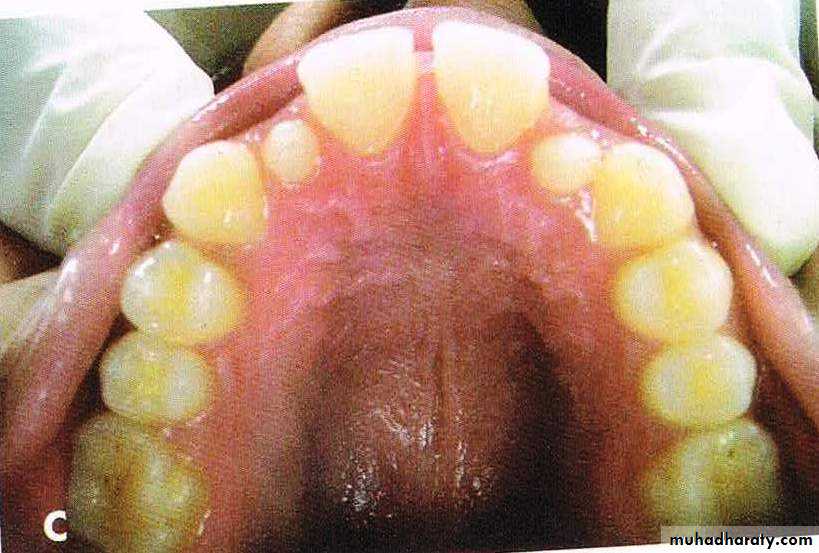

A, Bilateral constricted maxilla with upper midline shift; B, type 1 RME appliance in mouth;

C, end of expansion; D, correction of upper midline shift at end of retention period.